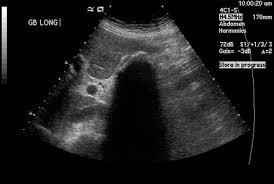

Criteria for distended GB

> 4 cm

Criteria for GB wall thickening

> 3 mm